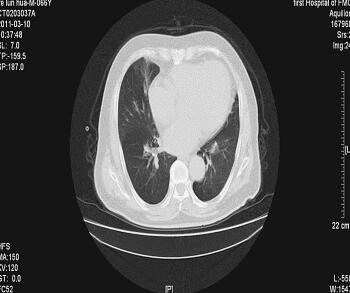

诊治经过:入院后查血常规:WBC 8.59×109/L,N 71.1%;血气分析:pH 7.387,PaO2 39mmHg,PaCO2 49.4mmHg;生化:空腹血糖7.30mmol/L,TC 5.18mmol/L,LDL-C 3.91mmol/L,CK-MB 18U/L;HbA1C 7.4%;CRP 8.69mg/L(0~8mg/L);PCT 0.09ng/ml(0~0.05ng/ml);D-二聚体139.8μg/L(< 342μg/L),GFR 93.44ml/min;BNP 363.65pg/L(0~100pg/L);肌钙蛋白I(TnI)2.406μg/L(0~0.78μg/L);电解质、肝肾功能正常;心电图:频速型房颤,左前分支阻滞,左心室肥大伴劳损,部分导联ST段抬高(图1);肺部CT:右肺中叶慢性炎症,心影增大,主动脉硬化(图2);肺功能检测:FEV1 26.9%,FEV1/FVC 90.1%。结论:混合型肺通气功能障碍。

图2 右肺中叶慢性炎症,心影增大,主动脉硬化